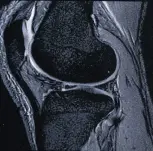

МРТ диагностика суставов, что дает расширенные возможности в установлении диагноза и в выборе тактики лечения.

МРТ лучезапястного сустава

Голеностопный сустав и стопа с сосудами